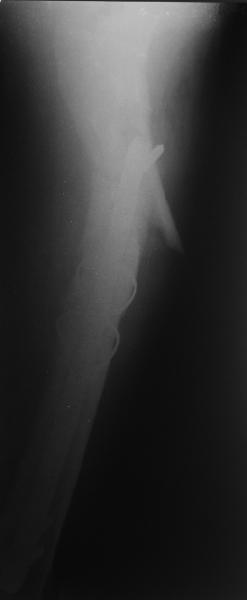

Зона раскола во время моей ревизии проходит по боковой поверхности как раз в зоне введения шеечного винта (картина как топор разрубил полено на две равных части, можа сделать КТ?)

ВБ> Длинная гамма?

ВБ> Зона раскола во время моей ревизии проходит по боковой поверхности как

ВБ> раз в зоне введения шеечного винта (картина как топор разрубил полено

Зона введения и вообще латеральная стенка тут не имеет значения, поскольку угловая стабильность обеспечивается самим фиксатором.

В общем, сделали. См. приложение.

Длина и из-за этого ось получились не совсем такие, как хотелось бы, все-таки срок после той операции уже 6 недель. Может быть, стоило провести дистракцию аппаратом неделю-другую. Заранее спасибо за комментарии и критику.